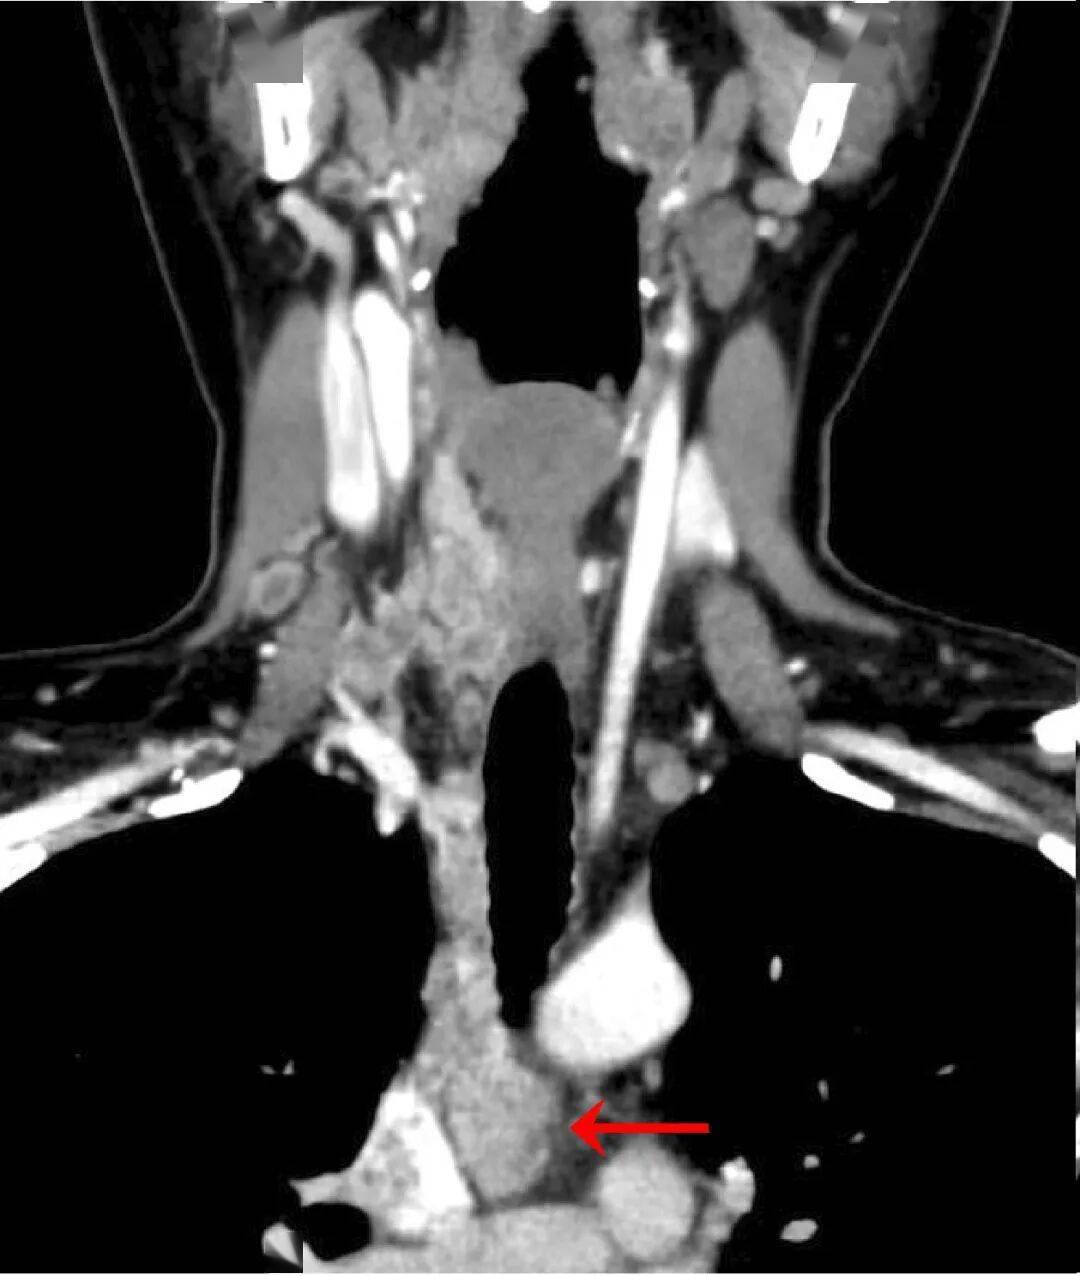

“朝阳医院给了我第二次生命!”术后已能下地活动的范女士(化名),对北京朝阳医院普外中心甲状腺颈部外科及多学科团队满心感激。38岁的她,曾因复杂凶险的甲状腺癌走到生死关头,而北京朝阳医院的医者凭借精湛技